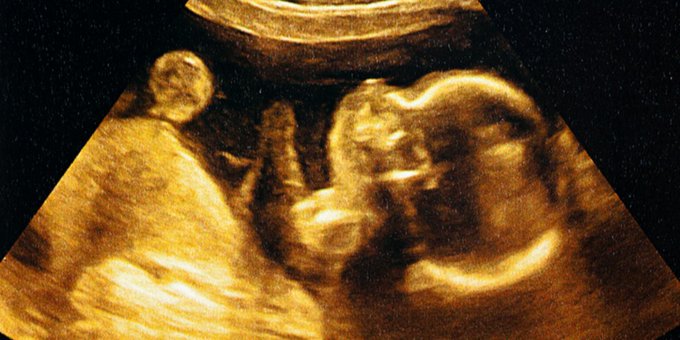

La edad gestacional es la edad de un feto o bebé. Pequeño para la edad gestacional significa que un feto o un bebé es más pequeño o está menos desarrollado de lo normal para su sexo y edad. Eso y más aquí ow.ly/yDDJ50z1dwG